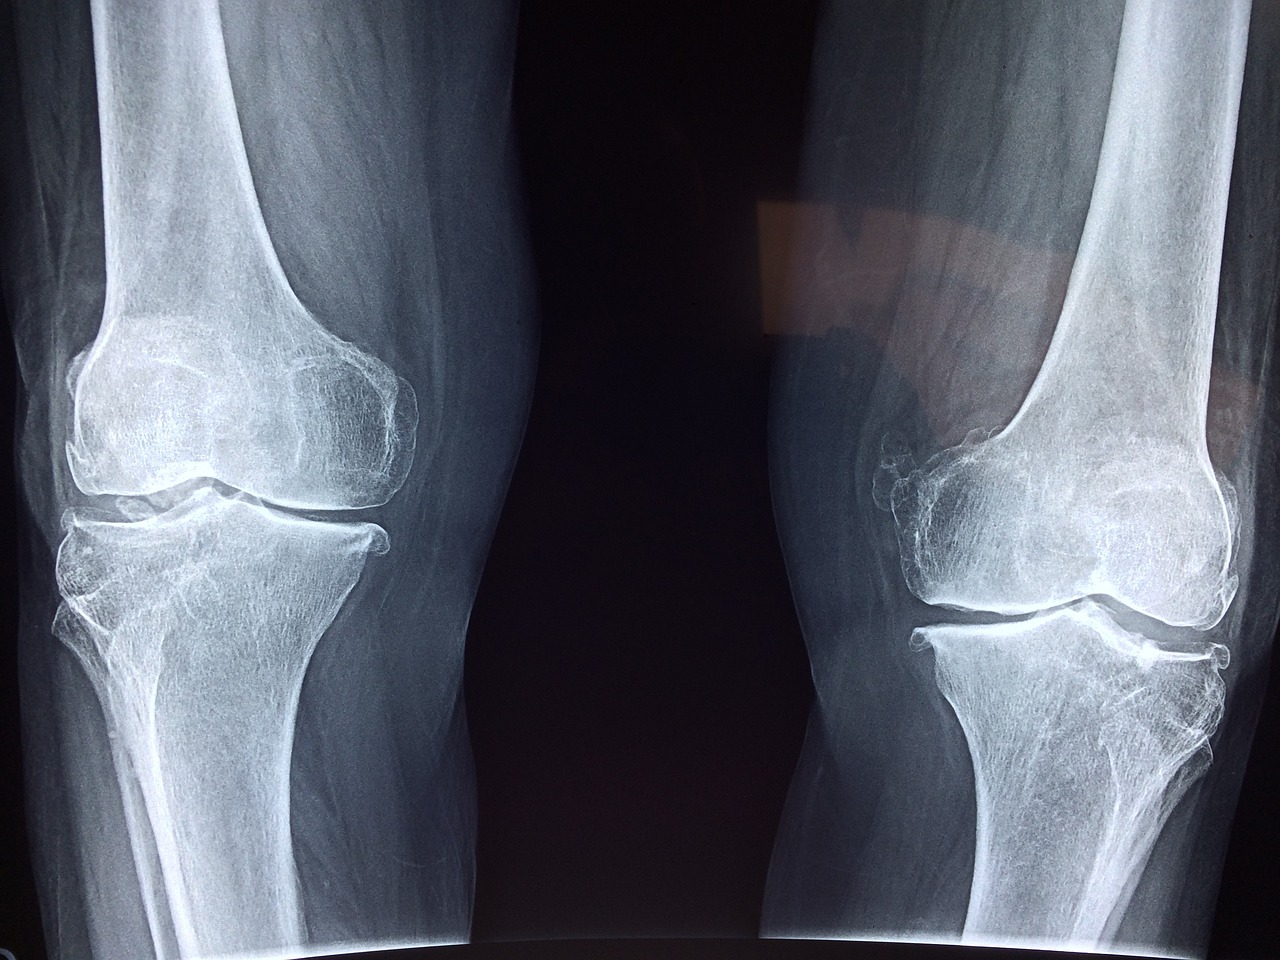

Bansal Global Hospital stands out as a premier Orthopedic Hospital in Ambala, we are committed to providing innovative and compassionate care for a wide array of musculoskeletal conditions.

We provide a comprehensive spectrum of orthopedic assessments and therapeutic interventions, catering to a wide spectrum of conditions...

Bansal Global Hospital is a distinguished Ortho surgical center an exceptionally specialized Orthopedic department.